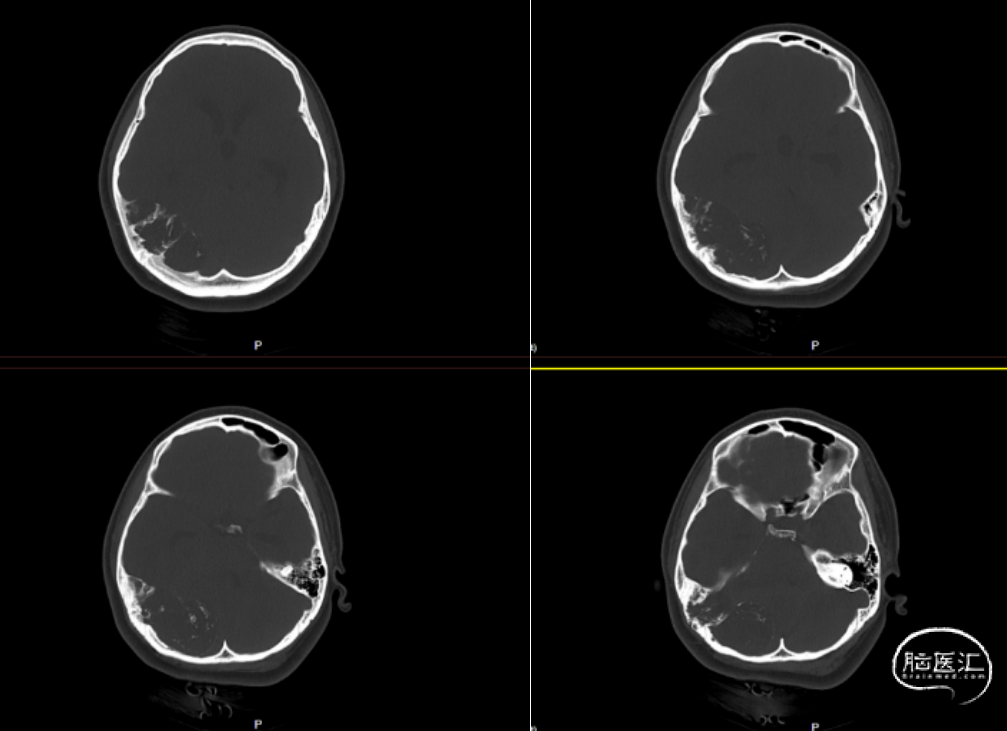

患者入院完善术前检查,头颅CT提示:右侧小脑半球-枕叶混杂密度肿块,大小约71*37mm,内见钙化,邻近颅骨骨质破坏、变薄,第四脑室受压(图1、图2)。进一步完善头颅增强MRI提示右侧颞枕部占位,脑外起源考虑,软骨肉瘤可能,血管瘤型脑膜瘤或血管瘤待排(图3)。

图2. 头颅CT骨窗像,见肿块邻近颅骨骨质破坏、变薄。

本例颅内软骨黏液样纤维瘤的影像学表现典型,CT与MRI可辅助术前评估肿瘤边界及与周围结构的毗邻关系。CT可清晰显示边界清晰的溶骨性病变,伴边缘硬化及周围骨结构改变,但钙化检出率较低(约13%),多见于颅面部CMF或年轻患者[1]。组织学中钙化检出率更高(约35%),颅底CMF的细胞内钙化比例可达75%[2],本例患者CT与组织学均证实钙化存在(图1)。 MRI在确定病变范围方面比CT更有效。肿瘤在T1加权像上呈低信号,T2加权像上呈高信号,增强后显著强化,周围可能有软组织肿胀。通常由于纤维、软骨样和粘液样成分的组成不同,T2-STIR或T2加权脂肪抑制图像显示中等到高信号[5]。此外,MRI能清晰显示病变周围正常血管结构,对制定手术方案至关重要[2]。